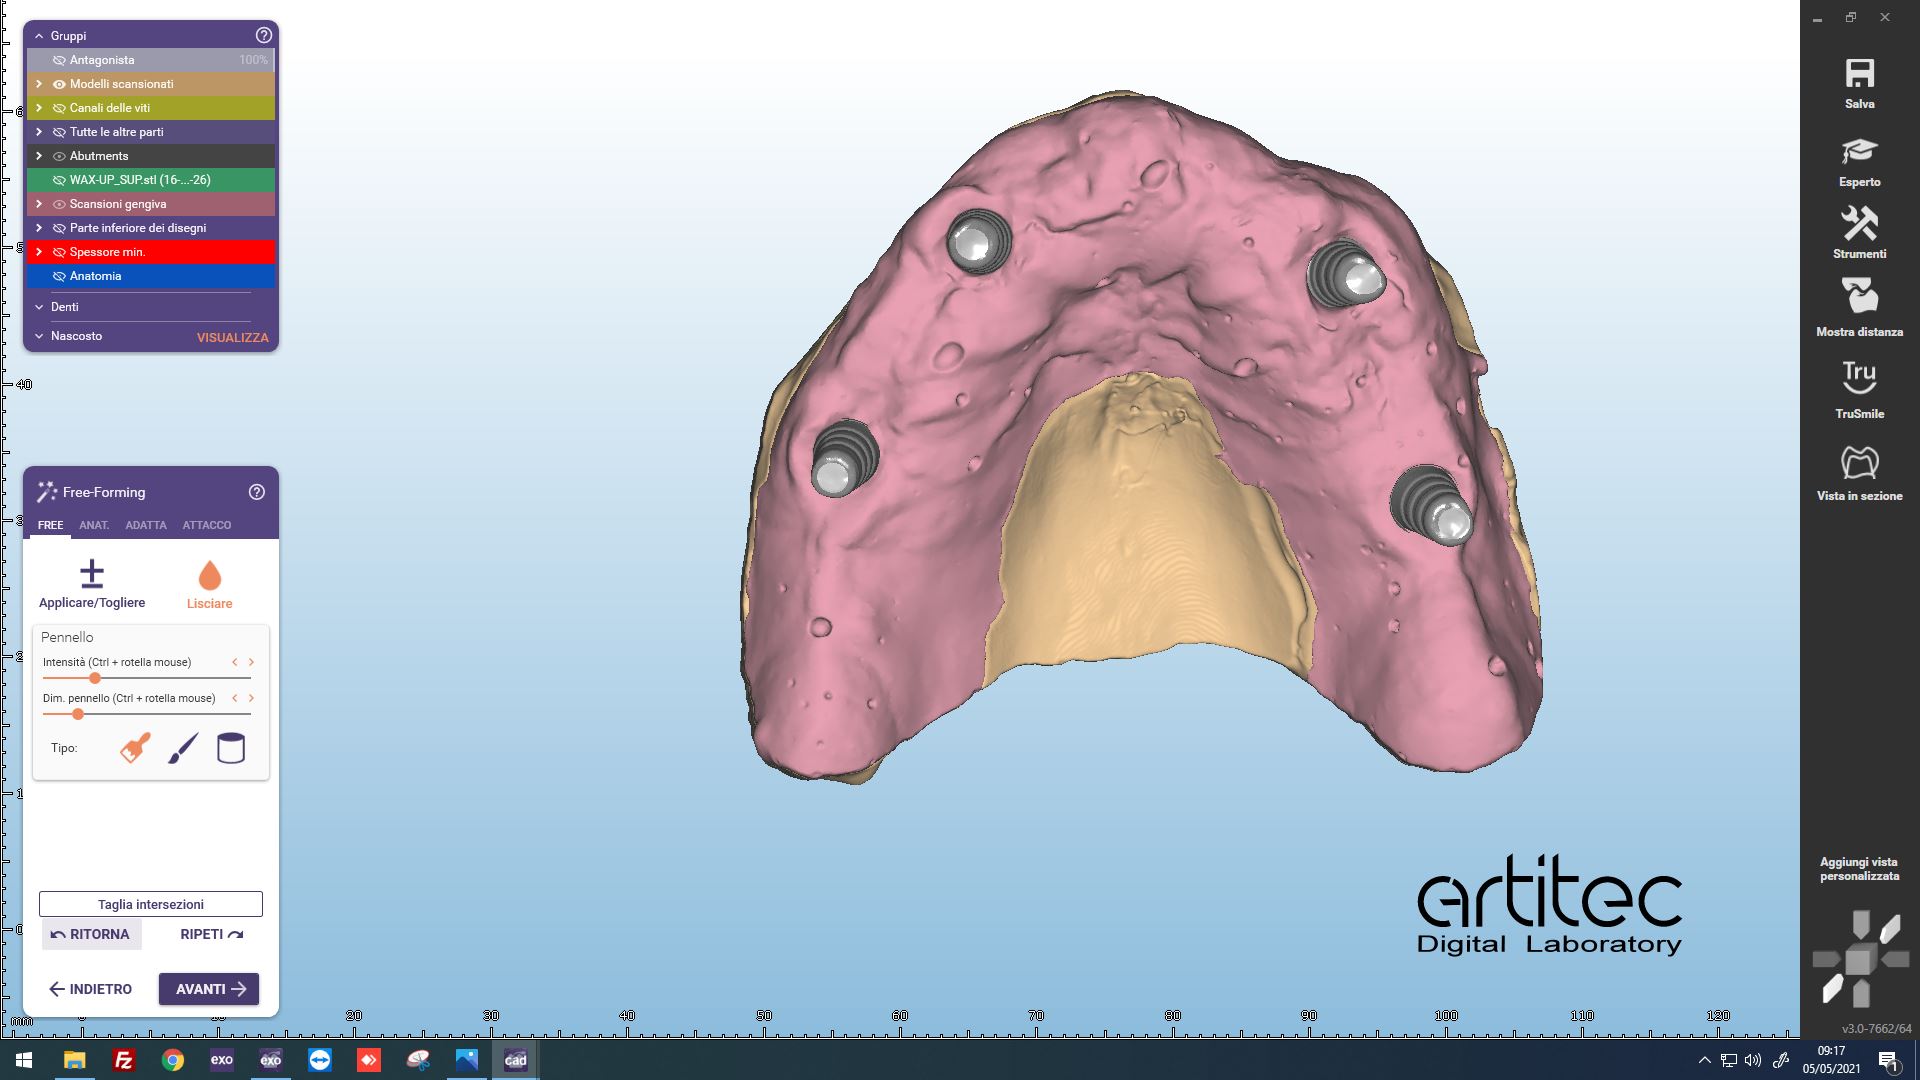

Fig. 6 Posizionamento anatomie CAD/CAM